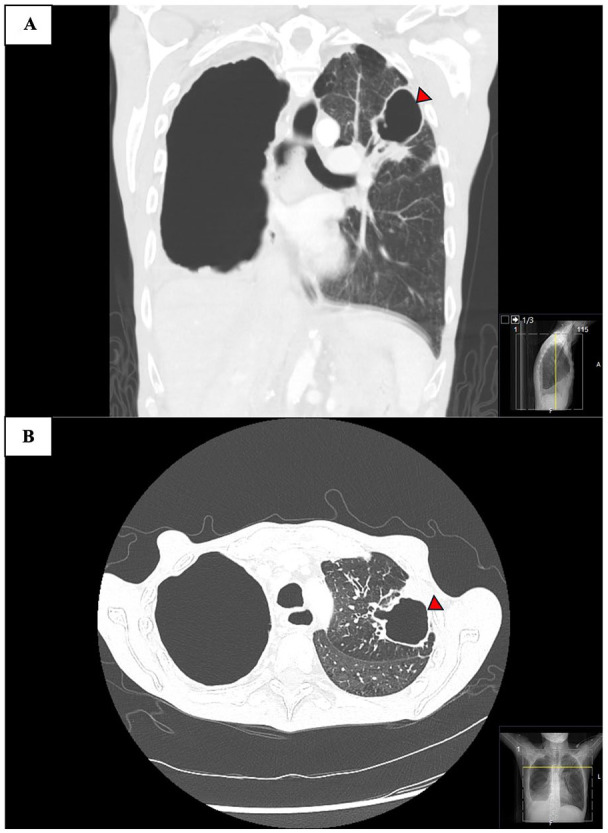

球孢子菌病是美国西南部的一种地方性疾病,可导致严重的肺部并发症,尤其是肺储备不良的慢性阻塞性肺疾病(COPD)患者。脓肿分枝杆菌易造成肺部结构性损伤,通常引起难以治疗的支气管扩张和空洞病变。我们报告一例58岁晚期慢性阻塞性肺病患者,30年前诊断为肺球虫菌病,入院前4年发现有脓疡分枝杆菌空洞性肺病的痰液和影像学证据,但未能随访。目前的表现是由于未经治疗的脓肿分枝杆菌感染的进展和潜伏的球虫感染的再激活。尽管开始进行抗真菌和抗生素治疗,但随后的过程因支气管胸膜瘘的发展和呼吸衰竭的恶化而复杂化,导致不利的结果。该病例强调了慢性阻塞性肺病患者并发感染的重叠临床和放射学特征以及破坏性结局相关的诊断挑战。及时的诊断检测和长期的综合治疗对于管理这种复杂的感染至关重要。

Coccidioidomycosis, endemic in the southwestern United States, can lead to severe pulmonary complications, particularly in chronic obstructive pulmonary disease (COPD) patients with poor lung reserves. Mycobacterium abscessus has a predisposition for structurally damaged lungs, commonly causing difficult-to-treat bronchiectasis and cavitary lesions. We present the case of a 58-year-old patient with advanced COPD and a remote history of pulmonary coccidioidomycosis diagnosed 30 years earlier, who was found to have sputum and radiographic evidence of M. abscessus cavitary lung disease 4 years prior to admission, but was lost to follow-up. The current presentation is attributed to the progression of untreated M. abscessus infection and reactivation of latent Coccidioides infection. Despite the initiation of antifungal and antibiotic therapy, the subsequent course was complicated by the development of bronchopleural fistula and worsening respiratory failure, leading to an unfavorable outcome. This case highlights the diagnostic challenges associated with overlapping clinical and radiologic features of concurrent infections and devastating outcomes in patients with COPD. Prompt diagnostic testing and prolonged comprehensive therapy are of paramount importance in managing such complex infections.